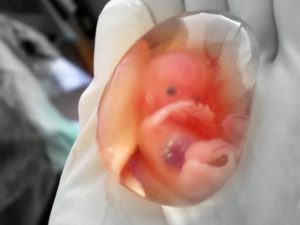

После отторжения плода, извлечения из полости матки, проводится тщательное его гистологическое исследование. Оно позволяет выявить серьезные пороки развития, которые могли стать причиной смерти зародыша.

Также анализу подвергается эпителий матки.

Такая диагностика позволяет с максимальной уверенностью установить возможные онкологические и другие заболевания внутренней репродуктивной системы у женщины, выявить инфекции, дисбаланс гормонов.